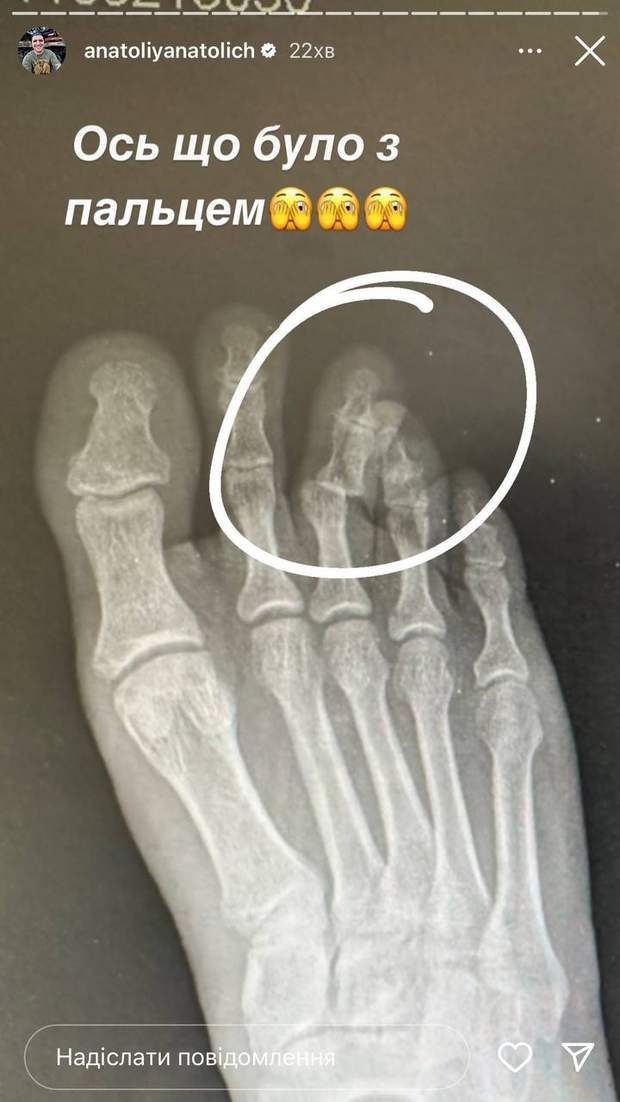

Шоумен розповів, що під час гри він сильно вдарився. Відтак Анатолічу викликали швидку та відвезли до травмпункту. Там його оглянули лікарі й наклали на ногу гіпс. З'ясувалося, що у ведучого перелом середнього пальця.

Зламав палець на футболі. Картина не для слабкодухих,

– сказав телеведучий.

Анатолій Анатоліч зламав палець на нозі / Скриншот з інстаграм-сторіс